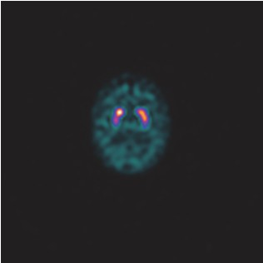

DaTSCAN is a brain scan to diagnose Parkinson’s disease. It involves an injection into your arm of a radioactive substance called DaTSCAN, which is taken up into various parts of the brain. It emits gamma rays which will be detected by a piece of equipment called a gamma camera. Depending on how it is distributed, we can differentiate Parkinsons syndromes with Essential tremor or Lewy body dementia with Alzheimer’s disease.